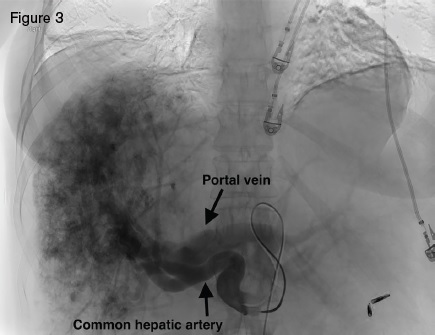

A 51-year-old woman with HHT was referred for management of recurrent epistaxis, GI bleeding, iron deficiency anemia, large bilobar hepatic AVMs, and worsening ascites. Gastric AVMs were previously managed with endoscopic argon plasma coagulation. She required regular intravenous iron and occasional blood transfusions to maintain a hemoglobin of seven to 10 g/dL. Elevated liver enzymes two years earlier prompted an ultrasound that demonstrated hepatic AVMs. Magnetic resonance imaging (Figure 2) demonstrated a macronodular liver with diffuse AVMs involving both hepatic lobes, ascites, and splenomegaly. Angiogram demonstrated large hepatic arteries with shunting primarily from hepatic artery to portal vein (Figure 3). She primarily reported weakness, dyspnea on exertion, and worsening ascites requiring weekly six- to seven-L paracentesis.

Angiogram displaying large hepatic arteries with shunting primarily from hepatic artery to portal vein.

Hepatic AVMs occur in as many as 74 percent of HHT patients.1 The majority of HHT hepatic AVMs, however, are asymptomatic, making routine screening inadvisable.2 Large hepatic AVMs with extensive arterio-hepatic venous shunting can lead to high-output cardiac failure. When shunting is predominantly between the hepatic artery and portal vein, presinusoidal portal hypertension can develop, leading to ascites and nodular regenerative hyperplasia. Hepatic angiography in our patient demonstrated a large, diffuse, bilobar hepatic AVM with hepatic artery-to-portal vein shunting. The hepatic AVM was thought to be the cause of our patient’s high-output cardiac failure, portal hypertension, and debilitating ascites.